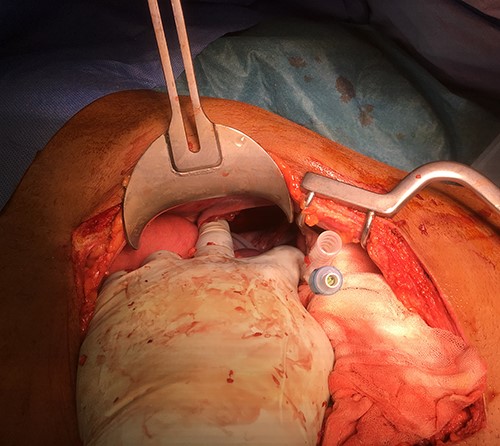

The patient was urgently taken to theatre for exploratory midline trauma laparotomy. Prophylactic antibiotics were administered. During surgery, a 10-cm defect of the left hemidiaphragm (Grade III [1, 2]) and 5-cm full-thickness stomach laceration (Grades II–III [3]) were identified along with contamination of the left hemithorax and abdominal cavity with a stomach content, a significant amount of chewed coconut (Figs 4 and 5).

Intraoperative photo after reduction of the ruptured stomach back to the abdominal cavity.

The spleen was intact. All recognised injuries of the diaphragm and stomach were repaired (0 Nylon for diaphragm and two layers of 3–0 Maxon for stomach) following extensive washout of thoracic and abdominal cavities. After the surgery, the patient was transferred to the intensive care unit (ICU) for monitoring. The intraabdominal and intrathoracic drains were removed on the 9th-day post-op.